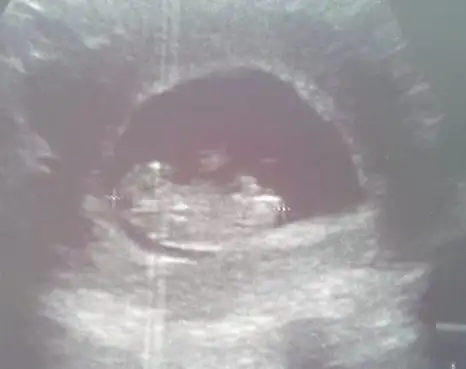

Diğer ultrason görüntülerini atıyorum, lütfen bide bunlara bakarmısın?

Eki Görüntüle 1277161 Eki Görüntüle 1277162

Canim yukari dogru bakan biaey var ama tam olarak nub mu gobek bagimi cozemedim bacaklariyla kapamis gibj:)Eki Görüntüle 1279243 Eki Görüntüle 1279245 Arkadaslar burda 12+5 gunluguz cok merak ediyorum tahmin de bulunabilirmisiz